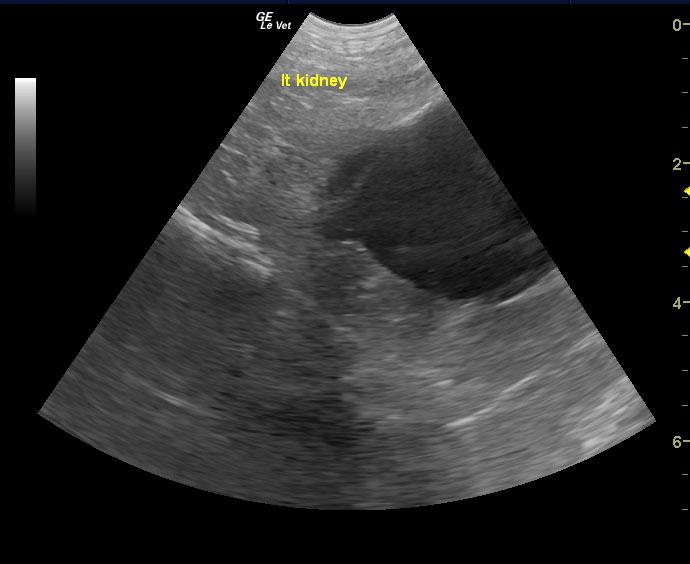

A 10-year-old SF American Eskimo with a history of bladder transitional cell carcinoma that had been stented, chronic renal insufficiency, hydronephrosis, and hydroureter, was presented for evaluation. CBC showed anemia (14%).